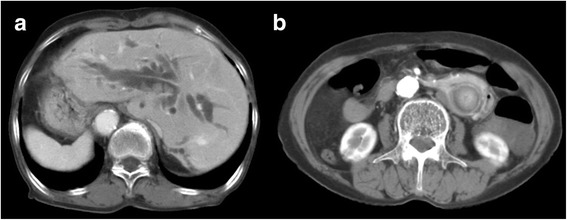

A 74-year-old woman presented with epigastric pain and jaundice for 3 days. She had epigastric tenderness but a negative Murphy’s sign. The aspartate transaminase level was elevated to 191 IU/L, the alanine transaminase level to 79 IU/L, and total bilirubin level to 15.23 mg/dL. The alkaline phosphatase level was 409 IU/L and γ-glutamyltransferase level was 815 IU/L. Computed tomography (CT) revealed diffuse dilatation of biliary tree, with multiple intrahepatic duct stones and common bile duct (CBD) stones (Fig. 1a). Previously undiagnosed situs inversus viscerum was also found on CT (Fig. 1b). Before performing ERCP, an endoscopic examination using conventional gastroscopy was performed, which showed a reversed anatomy of the gastrointestinal tract. For removal of bile duct stones, the patient was placed in the prone position and the endoscopists performed ERCP from the right side of the table. The endoscope was rotated 180° counterclockwise in the stomach. After entering the duodenum, the endoscope was again shortened using a 180° counterclockwise rotation (Fig. 2a,b, Additional file 1 and Additional file 2). Although access was relatively easy, the ampulla in the endoscopic view was deviated to right side and right-upward direction (Fig. 2c). Moreover, it was difficult to control the endoscope owing to the looped endoscope shaft. In the first ERCP, the cholangiogram revealed a large filling defect and diffuse dilatation of tge CBD. After performing a sphinterotomy and mechanical lithotripsy, we removed a bile duct stone. However, several stones still remained in the CBD on follow-up cholangiography.